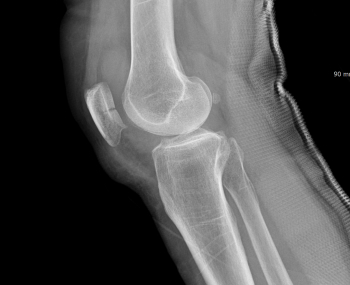

골절 부위가 관절과 가까우면 몇 mm 오차도 후유증으로 이어질 수 있습니다.

정확한 골절의 위치, 각도, 회전 방향까지 분석해 수술계획을 수립하고,

부위별 골절 특화 의료진이 직접 수술합니다.

• 골절 부정정합관절 변형, 관절염

• 늦은 진단수술 타이밍 놓쳐 비수술 어려움

특히, 골절 후 72시간(3일 이내)가 치료 성패를 가르는 골든타임입니다.